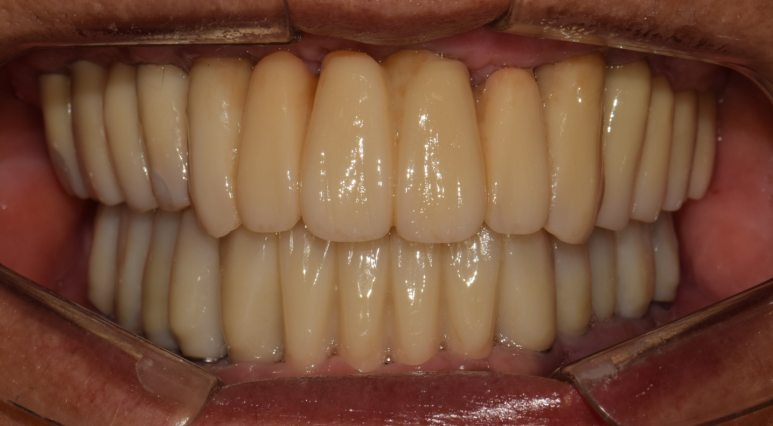

촬영일시 2024.09.01. 내원 당시 술전 파노라마 엑스레이 사진입니다. 환자분 안모 기준으로 좌측 작은 어금니 부위(#24,25번 치아 부위)를 제외한다면 뼈의 상태를 수술하기에 양호한 편에 속합니다. (저희는 이런 경우를 운동장 같은 뼈라고 비유하곤합니다 ㅎㅎ) 촬영일시 2024.11.01. 좌우측 어금니 부위에는 상악동거상술(수직접근법)을 동반하여 임플란트를 심어드렸구요. 앞니 부위는 뼈이식을 통해 뼈의 두께를 늘려드렸습니다. 처음 말씀드렸던 환자분 기준 왼쪽 작은 어금니 부위(#24,25 치아 부위)에도 뼈이식을 충분히 하여 골재생을 도모했습니다. 가이드나 스탠트의 도움이 전혀 없이 상악동 거상술 및 골이식을 포함하여 임플란트 9개를 식립하는데 대략 40분이 좀 안걸렸습니다. 임플란트간 위치와 기울기가 보기 좋게 식립되었습니다 ㅎㅎ (매일매일 하다보면 수술이란게 환자분들 걱정만큼 오래 걸리지 않습니다 ㅎㅎ) 임플란트가 좋은 위치에 식립되고 잘 완성된 모습입니다. 촬영일시 2024.12.10. 환자분께선 걱정을 많이 하셨는데 순식간에 끝났다며 좋아하셨습니다 ㅎㅎ 상악동 거상술 부위와 골이식 부위가 단단하게 굳는 기간 동안 무리하지 않도록 주의를 당부드렸습니다.